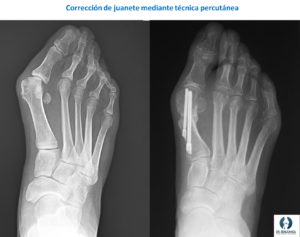

Existen múltiples técnicas correctoras de la deformidad. A nivel general encontramos dos tipos de procedimientos, aquellos que consisten en cirugía abierta y otros que se realizan de forma percutánea (cirugía láser del pie). Cada técnica aporta unas ventajas y unas desventajas. Lo ideal es ofrecer a cada paciente la técnica que más le convenga en cada caso.

- Cirugía percutánea (láser): Es una técnica que se realiza a través de pequeñas incisiones, respetando en mayor medida toda la vascularización del hueso y los tejidos blandos. La cirugía se guía a través de rayos X o de control ecográfico (Debajo os dejo un artículo que publicamos describiendo la técnica guiada por ecografía para la corrección de metatarsalgias). Realizar una cirugía percutánea permite una cicatrización más rápida y un menor riesgo de infección, lo cual es interesante en pacientes mayores, o con enfermedades que pueden causarnos problemas, como problemas de insuficiencia venosa o diabetes.